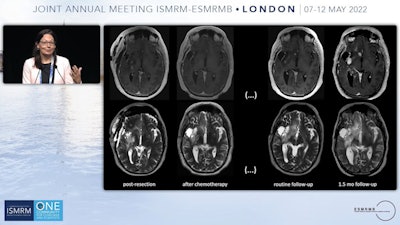

Smits provided an example of the type of patient who could benefit. She showed brain MRI scans of a patient whose tumor was resected, with no significant findings after chemotherapy. However, on a routine follow-up T2-weighted abnormalities appeared to increase, and a month later, another exam revealed the tumor had fully returned. Something happened to the tumor that made it nonresponsive to treatment, she said.

"We would like to know what changed because then of course we can adapt the treatments, and we won't be taking a tissue sample every time we follow these patients up," Smits said.